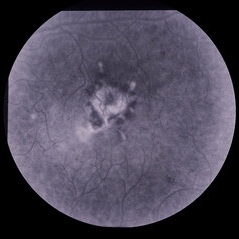

Fundus Fluorescein angiogram, ARMD. ARMD Laser Rx

Condition/keywords: neovascular age-related macular degeneration (AMD)